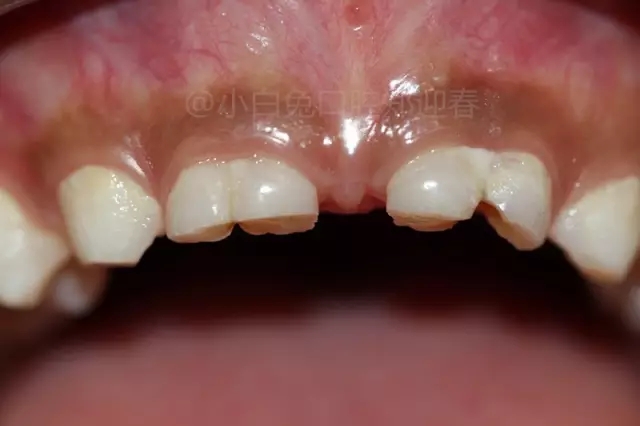

患兒,10歲,因上前牙未替換來診,查體:輕度反合,51和52、61和62均融合,且存在間隙約4mm,全面曲面斷層片顯示:11、21未萌,52、51、61、62牙根均有不同程度的生理性吸收。

拔出后的離體牙